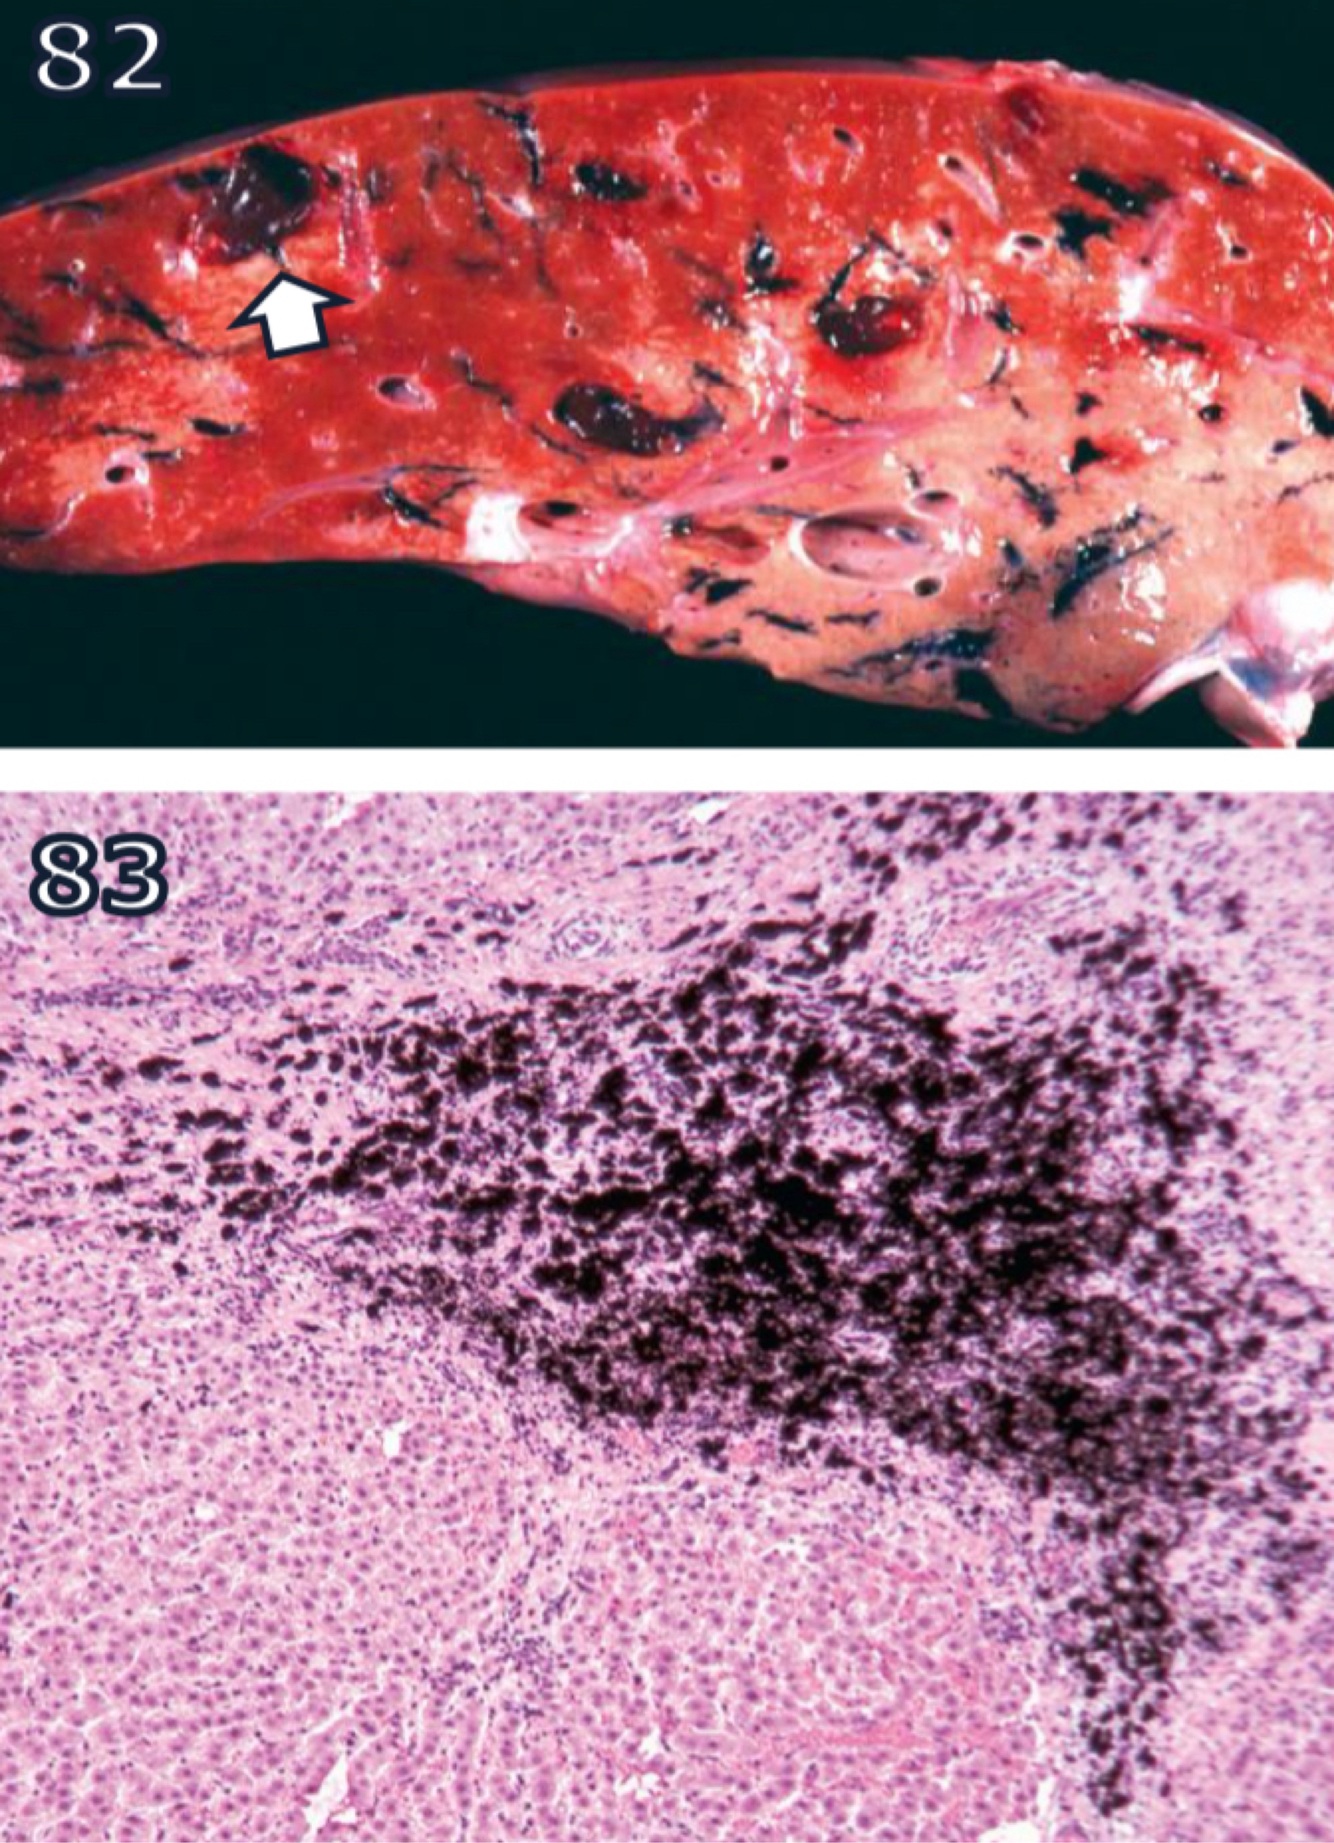

Parasitic Hematin

Hematogenous Pigments

A

prasites infecting or consuming RBCs liberate heme during proteolysis of Hgb

free heme is toxic but parasites have evolved to aggregate it into heme dimers

accounts for blacking of migration tracts by juvenile liver flukes in ruminants + for black speckling of lungs in macaques infested w/ lung mite